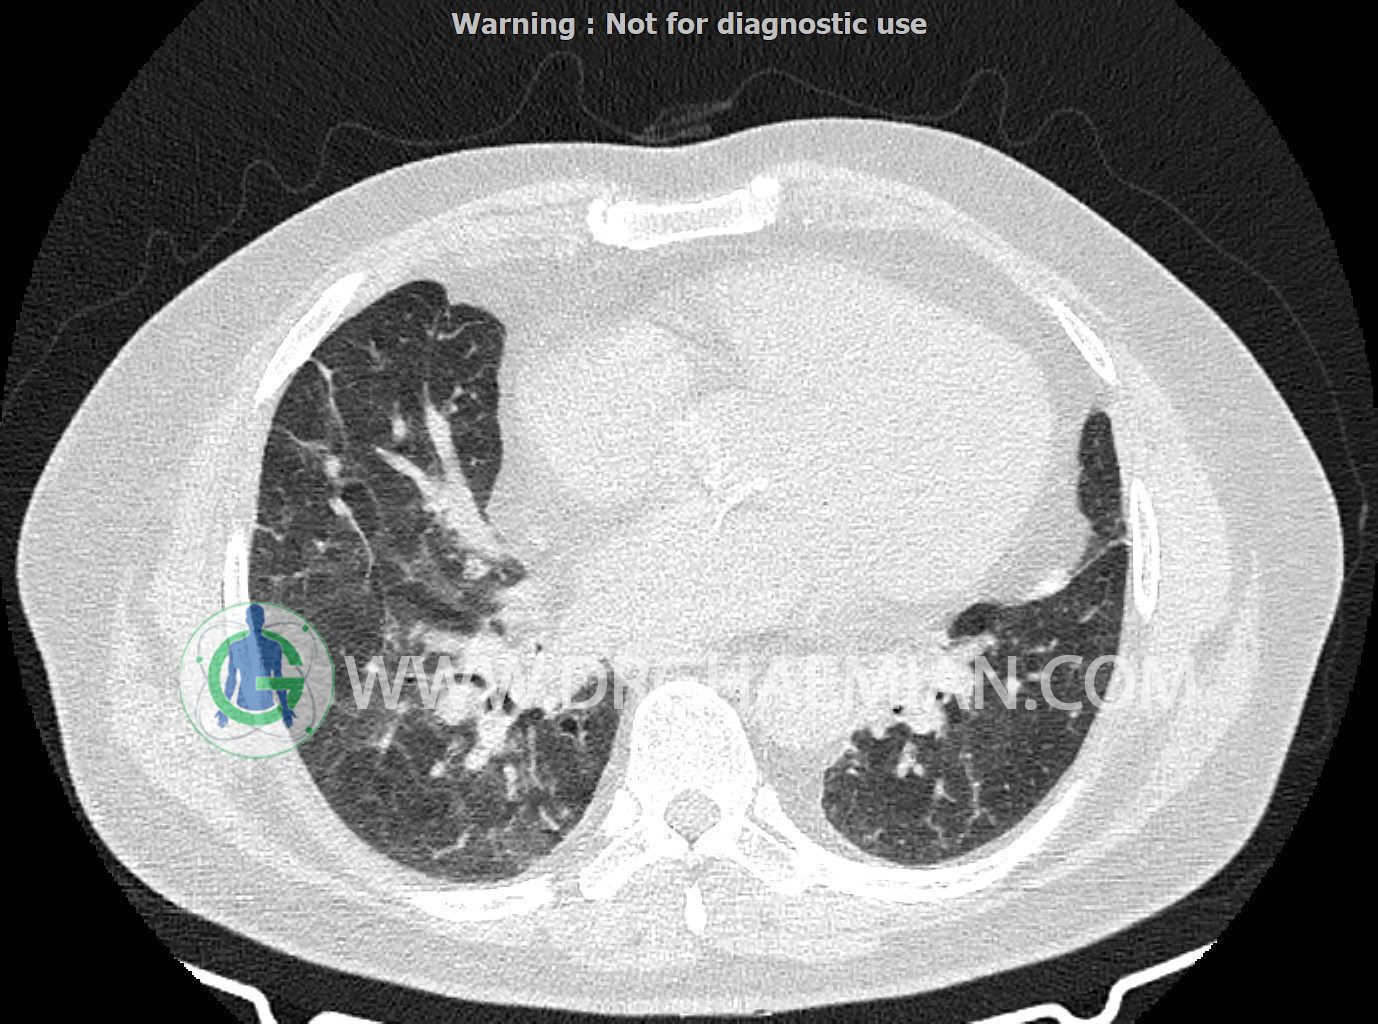

سی تی اسکن ریه یک روش تصویربرداری است که با استفاده از تشعشعات تصاویر عرضی مقطعی از ریه و بالا تنه ایجاد می کند. در این کیس کاردیومگالی،باندهای آتلکتازی و فیبروتیک پراکنده،کدورت های گراند گلاس،زمینه ی ادم قلبی (مراحل اولیه)،مشهده میشود.

در سی تی اسکن اسپیرال ریه ها و مدیاستن بدون کنتراست وریدی (مولتی دیدکتور 16 با مقاطع ظریف و بازسازی کرونال):

کاردیومگالی

باندهای آتلکتازی و فیبروتیک پراکنده در دو طرف

smooth septal thickening در لوب فوقانی ریه ها

peribronchial wall-thickening و عروق prominant در هیلوم دو طرف و کدورت های گراند گلاس دو طرفه

مشهود است.

شواهد فوق در درجه اول می تواند در زمینه ی ادم قلبی (مراحل اولیه) باشد.